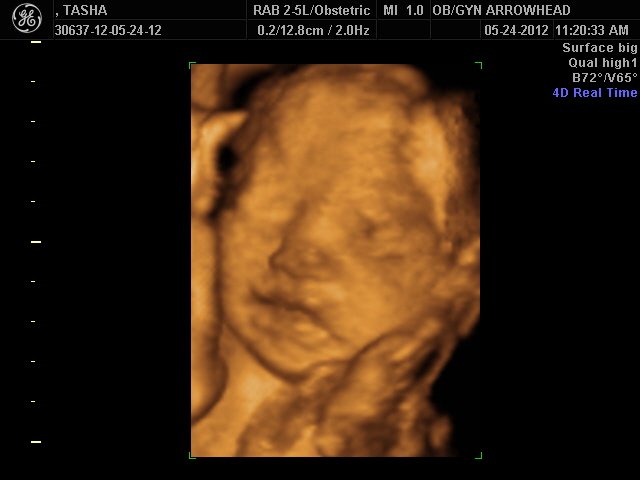

We offer complimentary 3D/4D Ultrasounds to all our OB patients around 30 weeks! The following photos are some examples of our work, shown with permission from our patients.